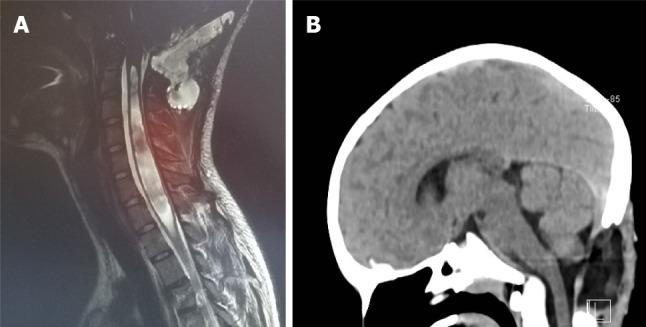

Chiari malformations encompass various radiological and clinical entities, sharing the herniation of the rhombencephalic structures through the foramen magnum as a common characteristic. They can be symptomatic or asymptomatic. The therapeutic strategies for these malformations differ on the basis of the diverse pathophysiologic processes that cause them. As Chiari malformations are caused by various pathophysiologic processes, they must be recognized promptly to select the best treatment for each single case.

Chiari畸形包括各种放射学和临床实体,其共同特征是菱脑结构通过枕骨大孔疝出。它们可以是有症状的或无症状的。这些畸形的治疗策略因导致它们的不同病理生理过程而异。由于Chiari畸形是由各种病理生理过程引起的,必须及时识别,以便为每个病例选择最佳治疗方法。